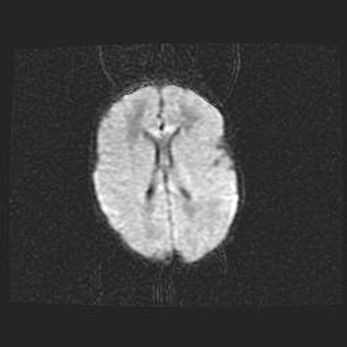

Лейкомаляция с кистозно-глиозной дегенерацией головного мозга.

Возраст: 2 месяца 25 дней

Вес: 6400 г

Окружность головы: 40 см

Срок гестации: 41 неделя

Лейкомаляцию относят к ишемически-гипоксическим повреждениям головного мозга, диагностируемым у новорожденных. При лейкомаляции в головном мозге обнаруживают очаги некроза, возникшие после тяжелой гипоксии и нарушения кровотока. В процессе морфогенеза очаги проходят три стадии: 1) развития некроза, 2) резорбции и 3) формирования глиозного рубца или кисты. Перивентрикулярная лейкомаляция (ПЛ) встречается примерно в 12% случаев среди новорожденных, обычно – у недоношенных детей, причем, частота ее зависит от массы, с которой младенец появился на свет. Наибольшее число малышей страдает лейкомаляцией, если масса при рождении 1500-2500 г.